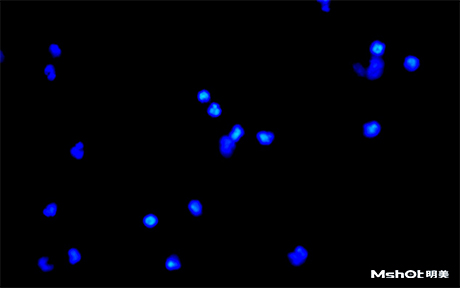

北京某试剂单位已有一台奥林巴斯生物显微镜BX61,希望能进行CTC检测,在电脑中成像拍摄保存图片,刚好我们在北京有办事处,工程师了解到具体需求分析后提供一款明美数字摄像头MS23,搭配奥林巴斯BX61生物显微镜在40X观察下,效果如图: